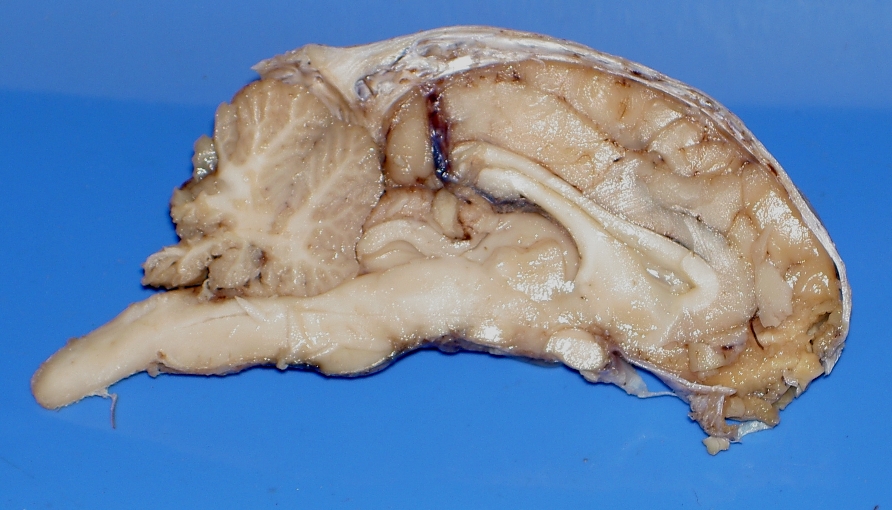

Images of Sheep Brains

These are unlabelled images of sheep brain dissections.

Use them to practice your identification of the listed structures.

3. coronal sections 2

8. sagittal section, L side